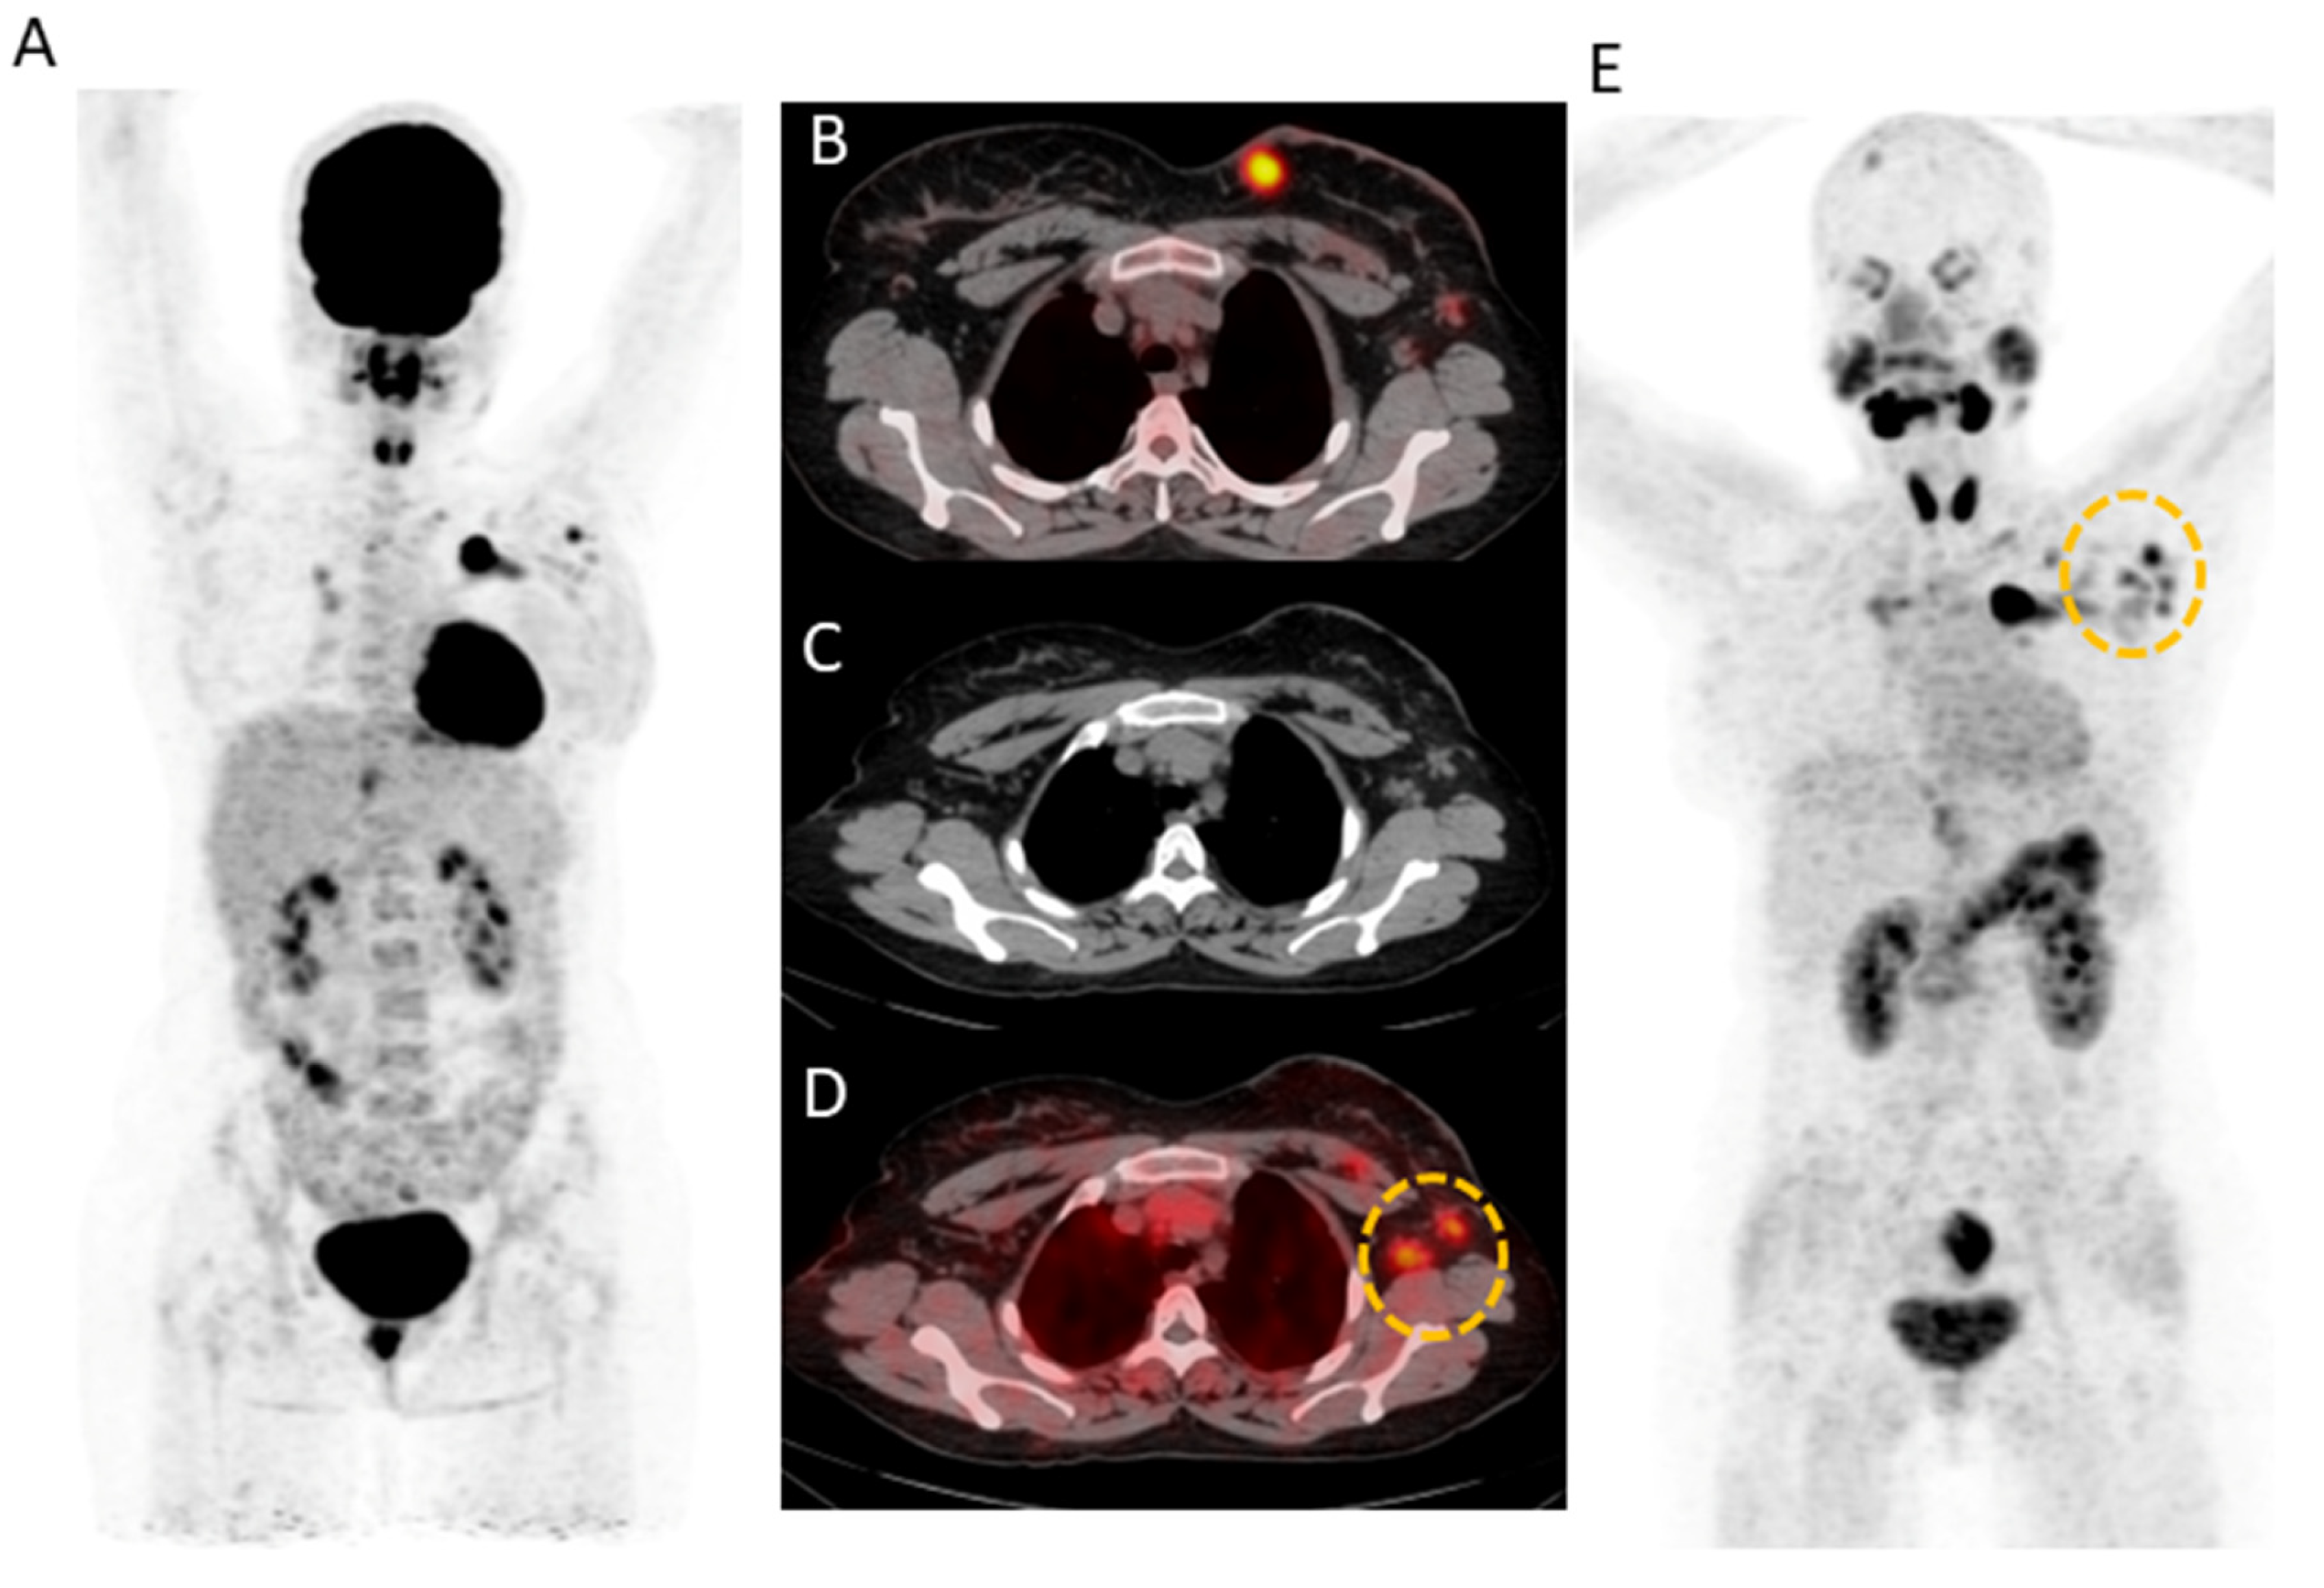

2. Results

2.2. Patient-Based Detection Rate Analysis

2.3. Lesion-Based Analysis